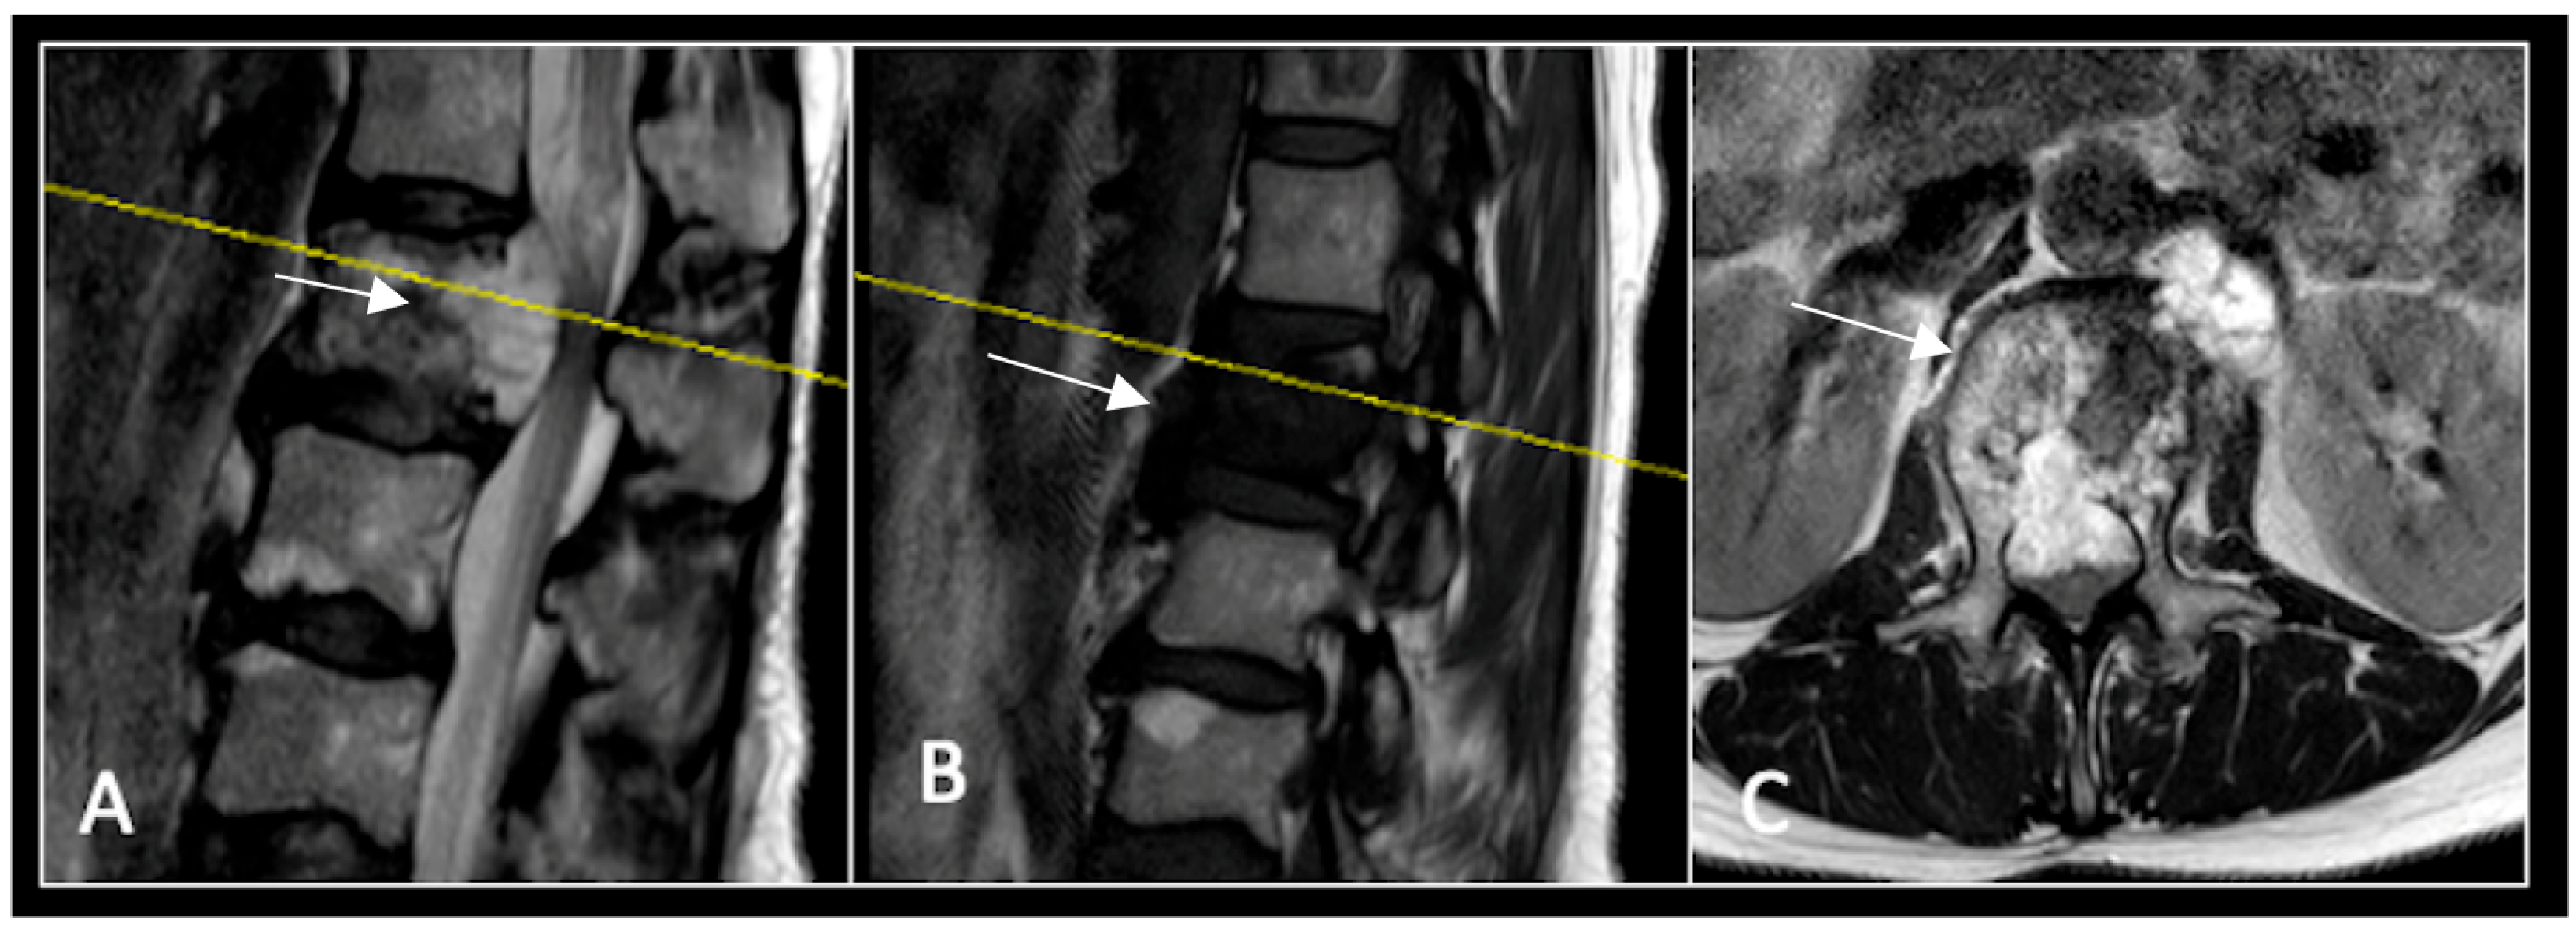

Figure 3.

RI post-separation surgery showing reduction in tumour (arrow) dimensions and circumferential decompression. The posterior elements have been removed, and a posterior occipitocervical stablilsation has been performed. En-bloc resection would have necessitated sacrificing the left C2 nerve root and vertebral artery. The yellow line on the sagittal images indicates the level of the corresponding axial section. (A) T2W sagittal; (B) T1W sagittal; (C) T2-W axial.